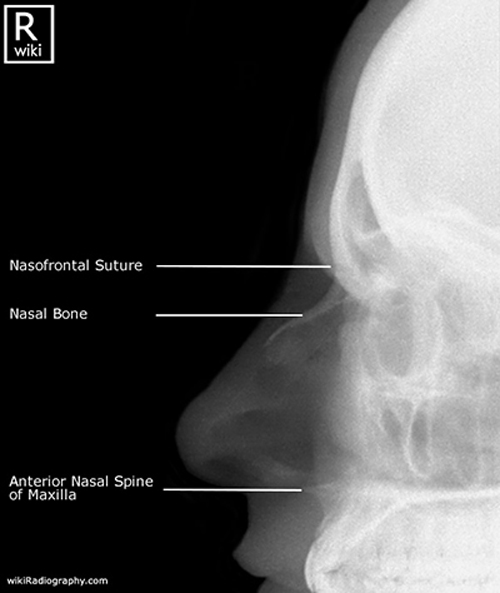

What is the most common facial fracture?

Nasal bone fracture.

What complication can a deviated septum cause?

Breathing difficulty.

Why is the nasal bone prone to fractures?

It is thin and prominent on the face.